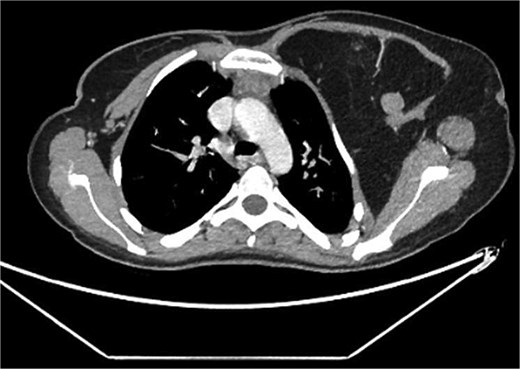

A 22-year-old female presented with progressive swelling in the left anterior chest wall above the left breast, associated with needle-like chest pain, left upper limb tingling, and weakness. The patient had a history of childhood cystic hygroma in the left axilla, previously excised. She denied constitutional symptoms but reported compressive symptoms such as shortness of breath, dysphagia, and hoarseness. A family history of breast cancer with thyroid metastasis was noted in her mother. On examination, the patient exhibited multiple bilateral solitary thyroid nodules and a bulky swelling in the left anterior chest and axilla. Computed tomography (CT) imaging (Fig. 1) revealed hypodense bilateral thyroid nodules, with magnetic resonance imaging (MRI) (Fig. 2) showing an enhancing left axillary lesion (2 cm, previously 1 cm) and an anterior chest wall lesion (1 cm). The mass, measuring 23 × 8 cm, extended to the lower left neck, left chest wall, and left axilla, encasing the neurovascular bundle without muscle or osseous invasion (Fig. 3). Fine-needle aspiration (FNA) cytology (Fig. 4) of the right thyroid nodule indicated atypia of undetermined significance (Bethesda III), while left-sided nodules and biopsies from the axilla, breast, and neck confirmed benign mature adipose tissue. The patient underwent total thyroidectomy, level V left neck exploration, and excision of lipomatous masses from the axilla, anterior chest, and breast, involving multiple surgical teams. Intraoperatively, vocal cords were preserved, and clear planes for lipoma excision were identified. The total excised lipomatous tissue weighed 13.57 kg (Fig. 5). Pathological examination confirmed mature adipose proliferation with no malignancy. Fluorescence in situ hybridization (FISH) ruled out MDM2 amplification, and genetic testing returned negative. Postoperatively, the patient developed deep vein thrombosis (DVT) in the left upper limb, diagnosed via Doppler study, and was treated with low-molecular-weight heparin (LMWH) followed by rivaroxaban. Follow-up MRI at 2 days and 3 months confirmed no residual or recurrent tissue growth. The patient started levothyroxine for thyroid function management and monitored for optimal dosing.

Partially scanned left thoracic lipomatosis extending to the lower neck with mild mass effect over the left internal jugular vein. A multilocular goiter with a complex thyroid nodule is noted in the lower neck.